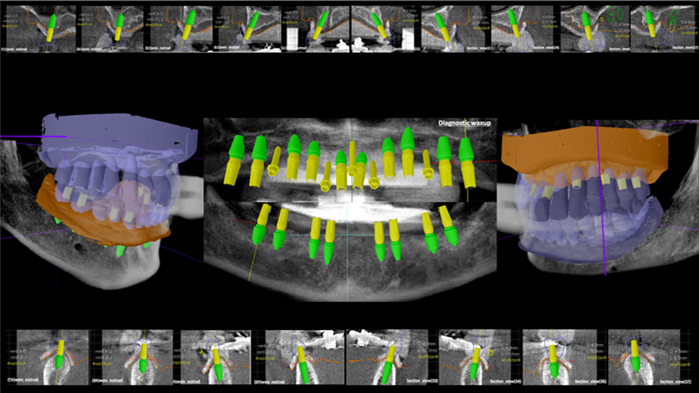

Dr. Sang Tack Lee, edentulous, digital full mouth prosthetics, digital guided surgery, #11, #13, #14, #16, #17, #21, #23, #24, #26, #27, #33, #34, #36, #37, #43, #44, #46, #47, guided surgery, flapless, AnyRidge, R2GATE, Mega ISQ, MEG Torq, MEG Engine, R2GATE Full surgical kit